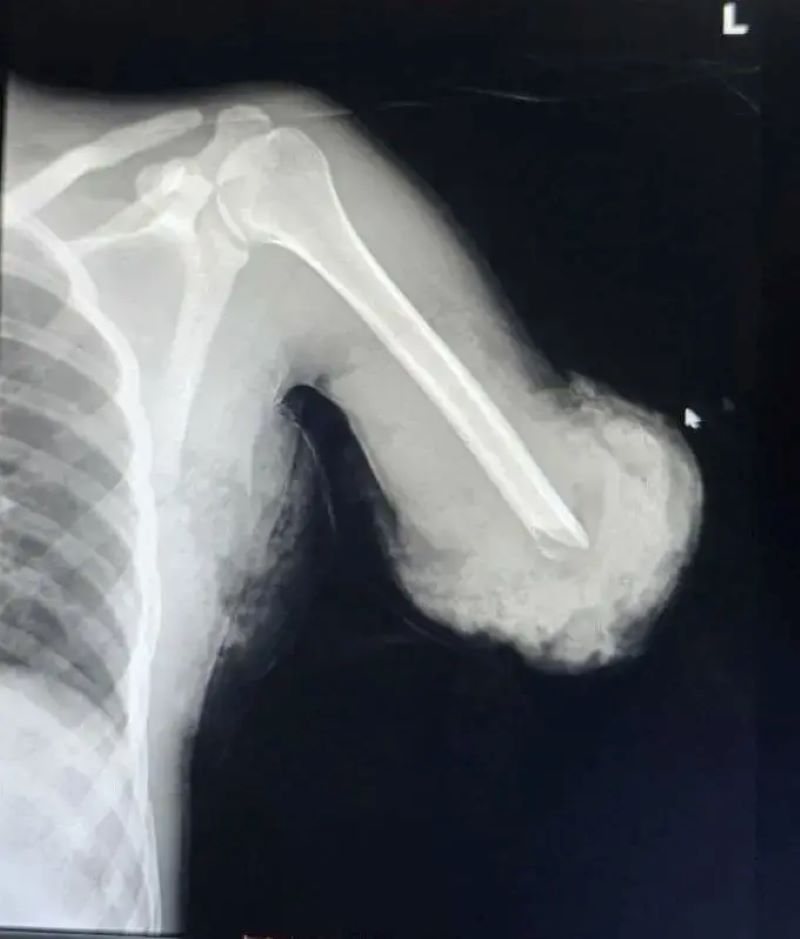

Ibi byabereye ku bitaro byigenga bya Samaritan Surgical Center biherereye i Addis Ababa, aho umusore yakiriwe nyuma y’impanuka yagize akaboko ke kugacikira hejuru y’inkokora mu gihe yakoraga akazi ko gukata imbaho. Dr Anteneh Hailu, umuganga w’inzobere wabigizemo uruhare, yabwiye BBC ko ako kaboko kari katandukanye burundu n’umubiri.

Kubaga kwakozwe mu byiciro bibiri bikomeye. Icyiciro cya mbere cyamaze amasaha atandatu, aho hibanzwe ku gusubiranya igufa n’imitsi minini itwara amaraso, kugira ngo akaboko kongere kubona amaraso no gufatirana n’umubiri. Icyiciro cya kabiri cyabaye nyuma y’ibyumweru bibiri, na cyo kimara hafi amasaha atandatu, hagamijwe kunoza ibisigaye birimo imikaya mito n’udutsi tw’imitsi.

Uyu muganga yasobanuye ko igufa ryacitse rishobora kongera gufatana iyo rihujwe neza, kimwe n’imitsi itwara amaraso ishobora kongera gukora, bigatuma igice cyari cyavuyeho gisubira mu buzima busanzwe buhoro buhoro.